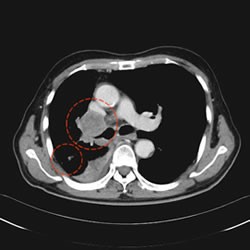

开始治疗后70日后(2个月半)(治疗 70天后)

*肺癌, 纵隔镜 淋巴结转移(71 岁男性)

来自中国的一名患者. 1疗程 5回 PD-1免疫抗癌剂(抗PD-1抗癌剂)

并用 免疫疗法NK・T细胞疗法 肿瘤减少了一半以上.

目前.以彻底消除肿瘤为目标.进行第2疗程的治疗.